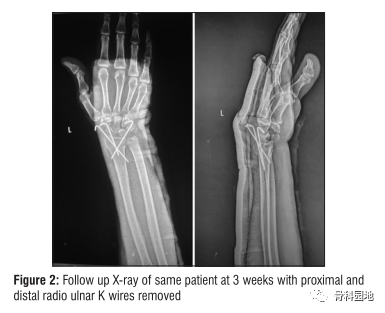

随访1、3、6、12周。第3周时,取下过肘夹板,改为不过肘夹板,取下尺桡线近端和远端的克氏针[图2]。

6周结束时,去除剩余的克氏针和夹板,并开始物理治疗[图3]。